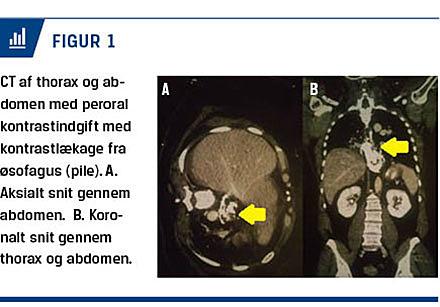

Objektivt var hun svært smertepåvirket, men hæmodynamisk stabil. Inspektion af collum afslørede subkutant emfysem, og abdominalundersøgelsen var præget af peritoneal reaktion med maksimal smerteangivelse i epigastriet. Dertil var et ophør af tarmlyde. Øvrige objektive fund var normale. En biokemisk undersøgelse viste leukocytose 12,4 × 109 mmol/l, med neutrofil overvægt 7,18 × 109 mmol/l. Initialt C-reaktivt proteinniveau var under 3 mg/l. Ekg’et viste sinusrytme frekvens 97, højredrejet akse, smalle QRS-komplekser og ingen tegn til iskæmi. På grund af patientens anamnese og objektive fund blev der rekvireret en CT af thorax og abdomen med samtidig peroral kontrastindgift på mistanke om øsofagusruptur (Figur 1).

CT’en viste luft i mediastinum dissekerende op på halsen og ned i abdomen samt kontrastlæk ud i mediastinum og sparsom mængde kontrastvæske i ventriklen. Patienten blev herefter overført til thoraxkirurgisk afdeling. Defekten i øsofagus blev først lokaliseret ved øsofagoskopi. Herefter blev der foretaget højresidig

torakotomi, stentning af øsofagusdefekten og anlæggelse af mediastinale dræn. Hun blev udskrevet ti dage senere.